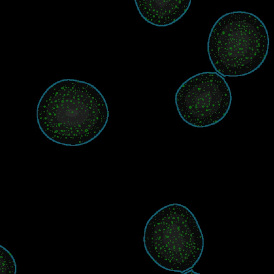

The IF Dots App provides dot detection per cell within the cell compartments for up to four markers in a sample (e.g., FISH, RNA, oil droplets). Each segmented cell compartment is measured for up to 20 intensity, statistic, and morphometric parameters. Dot measurement parameters are provided per cell compartment (e.g., nucleus, cytoplasm) and per dot and include count, mean intensity, total dot area, the sum of intensity.

App Category 2